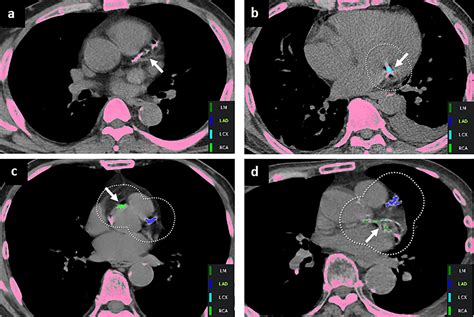

Artificial Intelligence in Coronary Artery Calcium Scoring Detection ...

4291Γ—1658